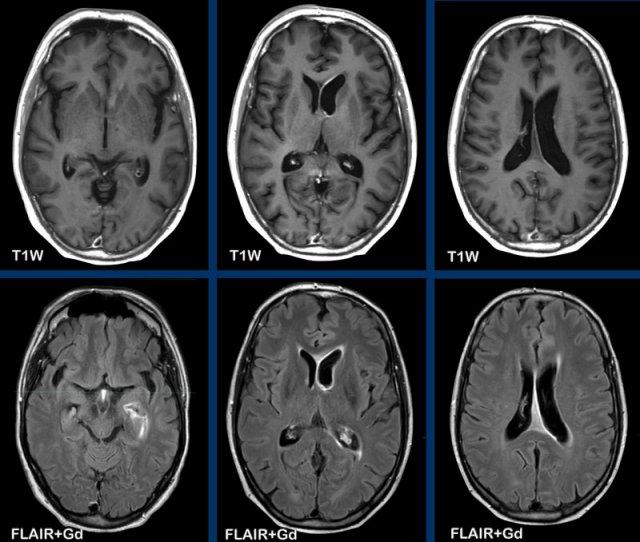

Các hình ảnh này của một phụ nữ 76 tuổi, có biểu hiện lú lẫn sau khi ngã.

Hãy quan sát các hình ảnh trước rồi mới tiếp tục đọc.

Câu hỏi:

- Chẩn đoán có khả năng nhất là gì?

- Những dấu hiệu nào điển hình cho chẩn đoán này?

Các dấu hiệu bao gồm:

- Tổn thương tăng tỷ trọng trên CT không tiêm thuốc cản quang kèm phù não do mạch máu.

- MRI cho thấy nhiều tổn thương ngấm thuốc dạng đặc và hạn chế khuếch tán.

- Trên chuỗi xung T2W, các tổn thương biểu hiện giảm tín hiệu.

- Một tổn thương nằm ở thể chai và một tổn thương khác nằm cạnh não thất.

Tất cả các dấu hiệu này đều điển hình cho u lympho nguyên phát hệ thần kinh trung ương, khác với u lympho hệ thống.

Các khối u này chiếm 6-7% tổng số u hệ thần kinh trung ương và mô học là u lympho tế bào B không Hodgkin.

Chúng thường nằm ở vùng cạnh não thất dưới màng nội tủy, thể chai và hạch nền.

Luôn nghĩ đến u lympho khi gặp tổn thương ngấm thuốc dạng đặc nằm gần não thất.

Hình ảnh tăng tỷ trọng trên CT, giảm tín hiệu nhẹ trên chuỗi xung T2W cũng như hạn chế khuếch tán được giải thích là do mật độ tế bào dày đặc của mô u lympho.

Ở bệnh nhân suy giảm miễn dịch, kiểu ngấm thuốc có thể là dạng vòng nhẫn.

Bệnh nhân này có nhiều phù não, nhưng trong nhiều trường hợp phù não rất hạn chế.